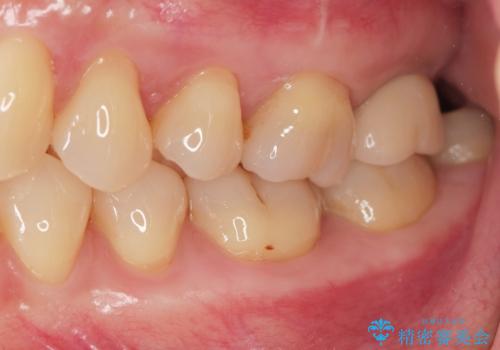

噛むと歯が疼く 歯牙破折からのインプラント治療

- 噛むと歯が疼いて痛い、と根管治療を希望され来院されました。

精査した結果、上顎奥歯は歯が割れてしまっており、根管治療ではなく抜歯の対象でした。

歯の抜去後、しっかりと咬合機能を回復するためインプラントを用いた治療を行っていきます。